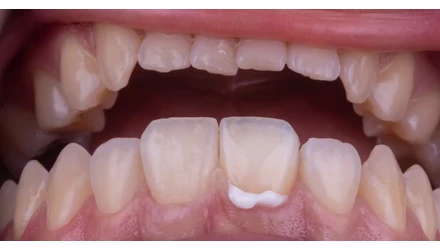

| A ragasztás maga a háromkomponensű PANAVIA™ V5 cementtel történt (23–28. ábra): Az előkészített fogstruktúrát és a felépítményt a PANAVIA™ V5 Tooth Primer-rel kezelték, a korona belső felszínét pedig a CLEARFIL™ CERAMIC PRIMER PLUS-szal. Végül a PANAVIA™ V5 Universal (fehér) cementet kinyomták a koronába, majd a koronát a helyére illesztették. A felesleges cementet a legjobb a gél fázisban eltávolítani – azaz a végső fényre keményítés előtt, 3-5 másodperces rövid polimerizáció után. Alternatív megoldásként közvetlenül a restauráció behelyezése után is eltávolítható ecsettel vagy hasonló eszközzel. Ebben az esetben az első lehetőséget választották. A kezelés eredményét a kofferdám eltávolítása, valamint a végső klinikai és esztétikai értékelés után a 29. ábra mutatja. |

29. ábra. A kezelés eredménye közvetlenül a kofferdám eltávolítása után. |

KonklúzióA beavatkozás célja egy traumásan sérült fog megőrzése volt – mind funkcióban, mind esztétikában. A sikerhez kulcsot jelentett a CLEARFIL MAJESTY™ ES-2 Premium erős, stabil alapja és a PANAVIA™ V5 egyik legmegbízhatóbb ragasztórendszere kuraraynoritake.eu. |